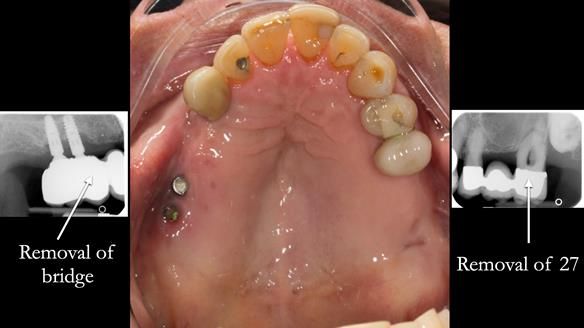

In the upper arch:

- a failing upper left tooth supporting a bridge was removed

- an implant-supported bridge on the upper right was dismantled

A metal-based upper RPD was made,

with metal backings incorporated to future-proof the design

should further teeth fail.